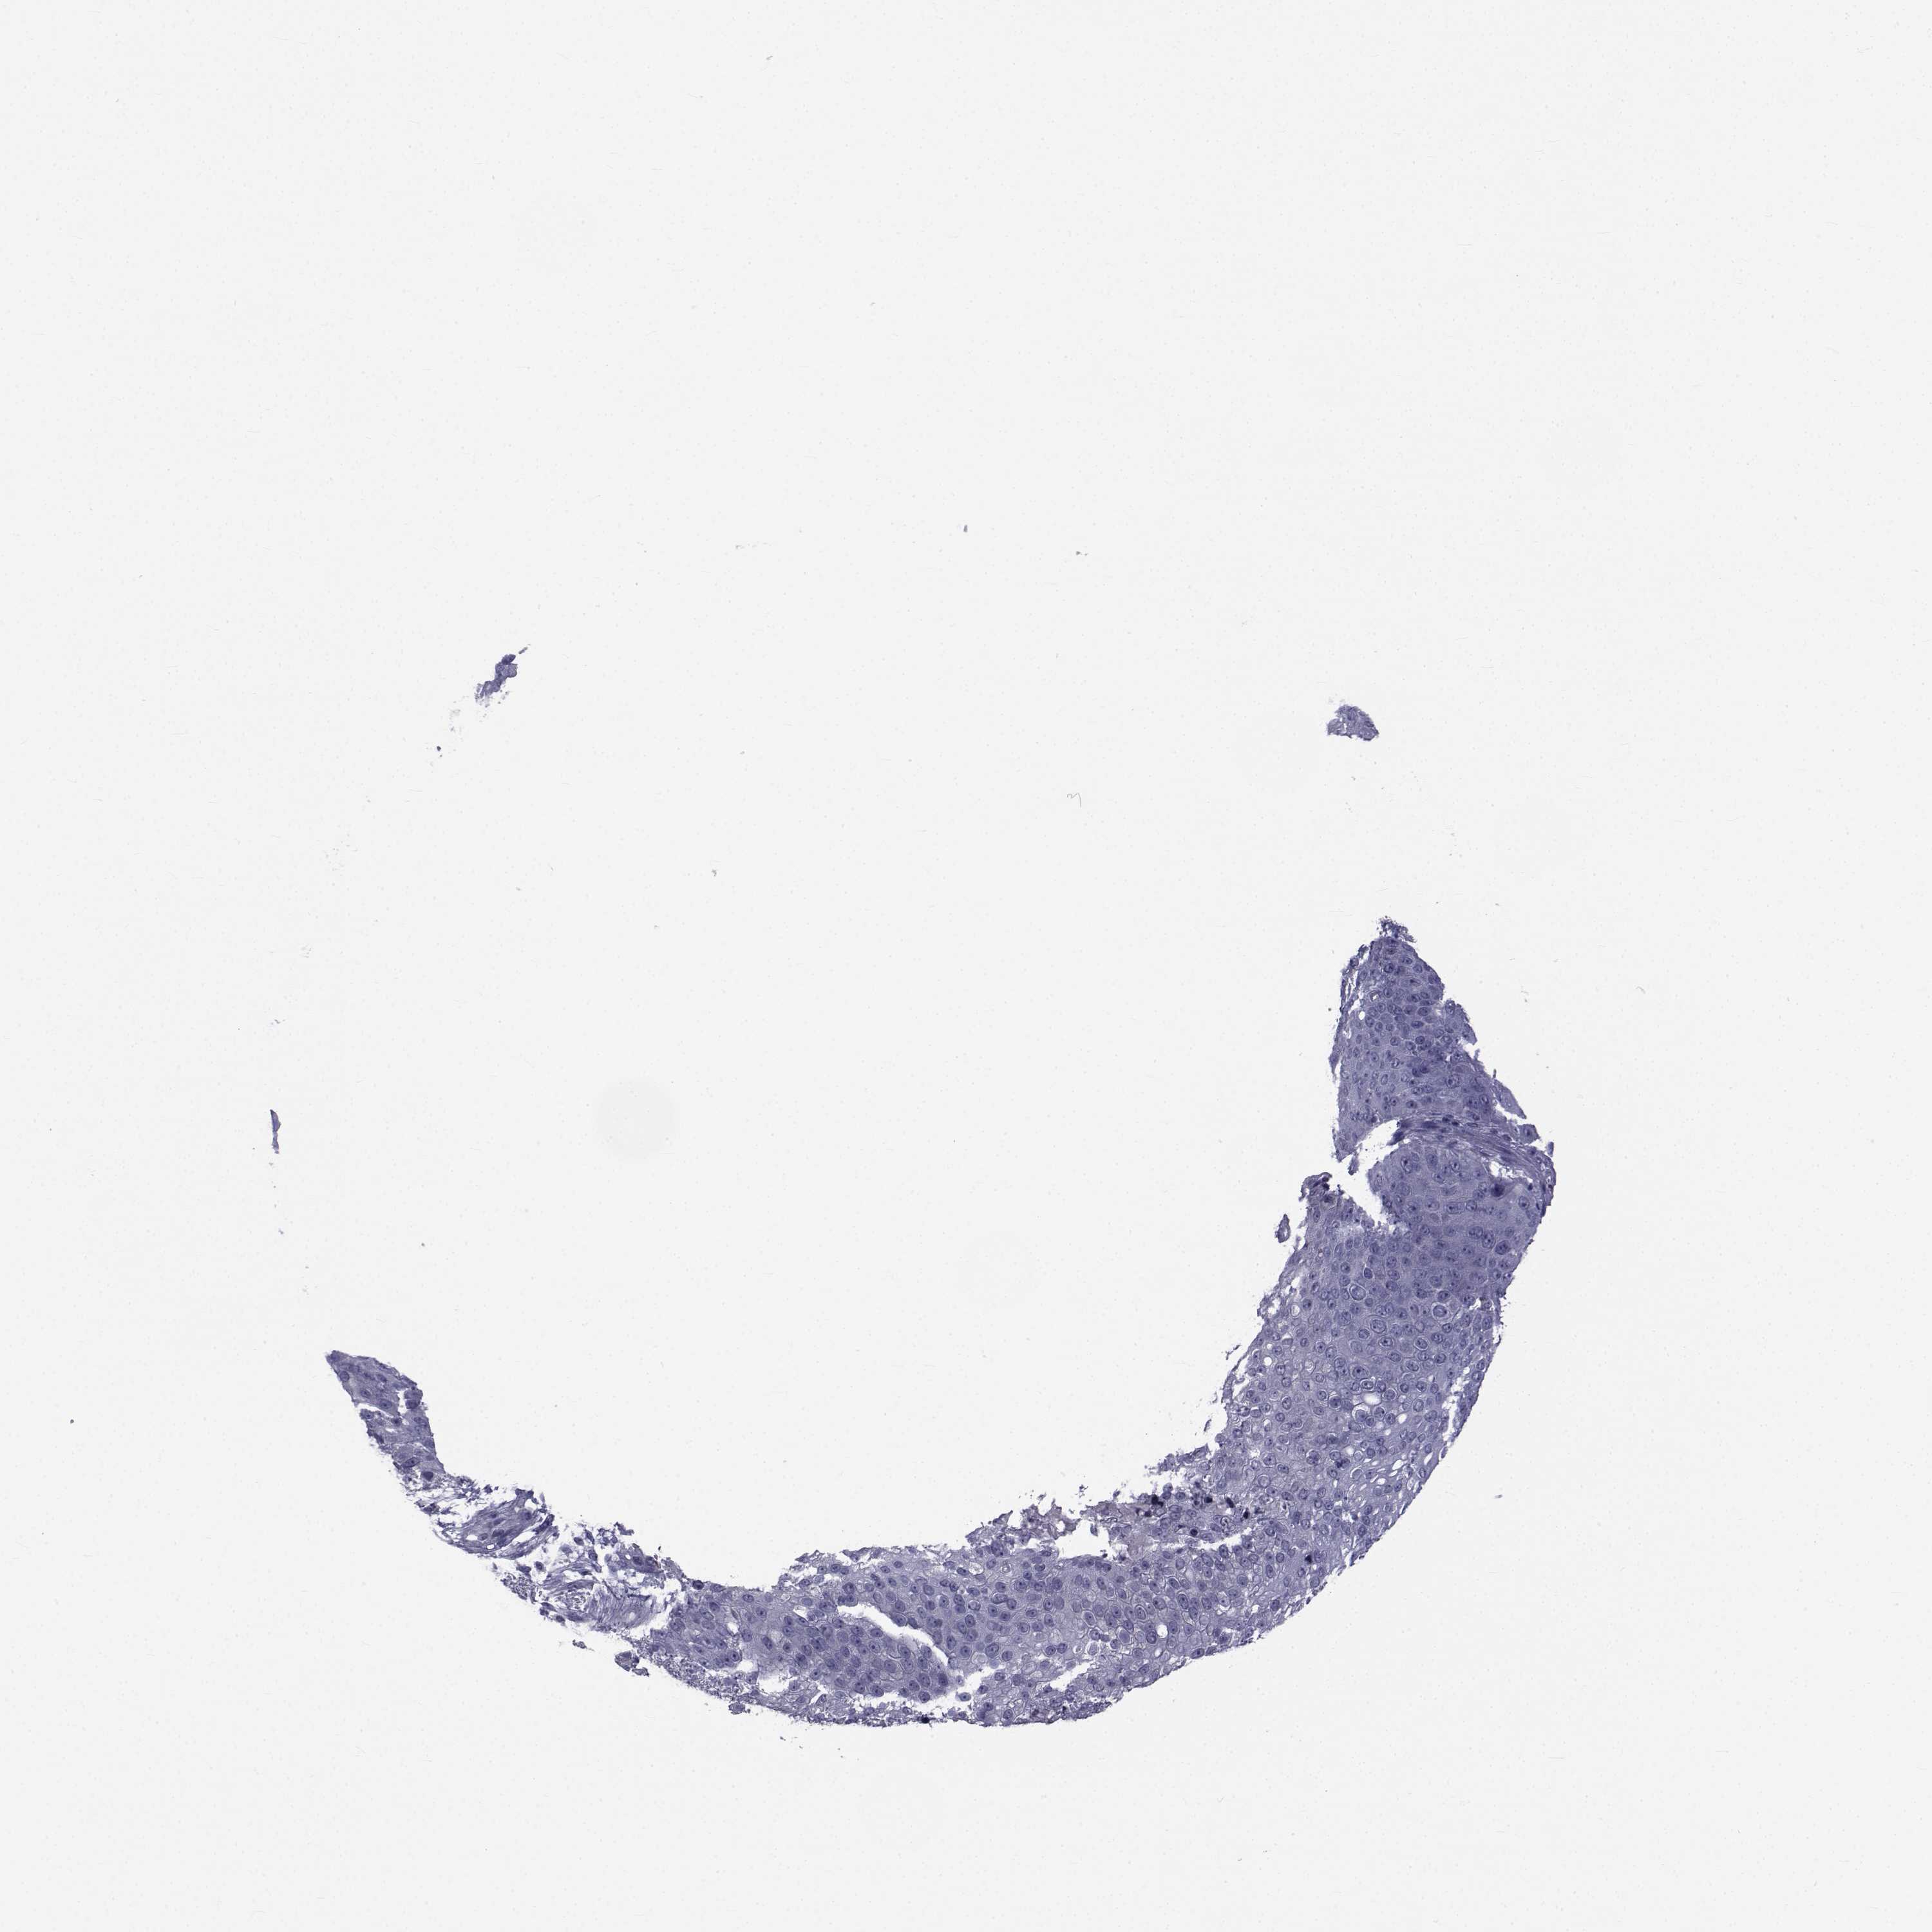

SKIN CANCER - Protein expressioni

A mouse-over function shows sample information and annotation data. Click on an image to view it in a full screen mode. Samples can be filtered based on level of antibody staining by selecting one or several of the following categories: high, medium, low and not detected. The assay and annotation is described here.

Each image is clickable and will lead to virtual microscopy that enables deeper exploration of all samples and also displays staining intensity scores, fraction scores and subcellular localization as well as patient and tissue information for each sample.

Antibody HPA044393

Antibody HPA053673

Antibody CAB009818

Staining

High

Medium

Low

Not detected

Intensity

Strong

Moderate

Weak

Negative

Quantity

>75%

75%-25%

<25%

None

Location

Nuclear

Cytoplasmic/membranous

Cytoplasmic/membranous,nuclear

Squamous cell carcinoma, NOS

Basal cell carcinoma